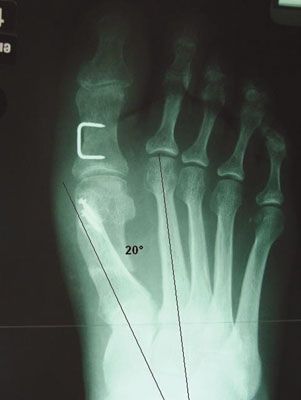

Technique Traitement chirurgical de l'hallux valgus par mini-abord , M. Benichou Montpellier N°159 - Décembre 2006 ● 10 min de lecture